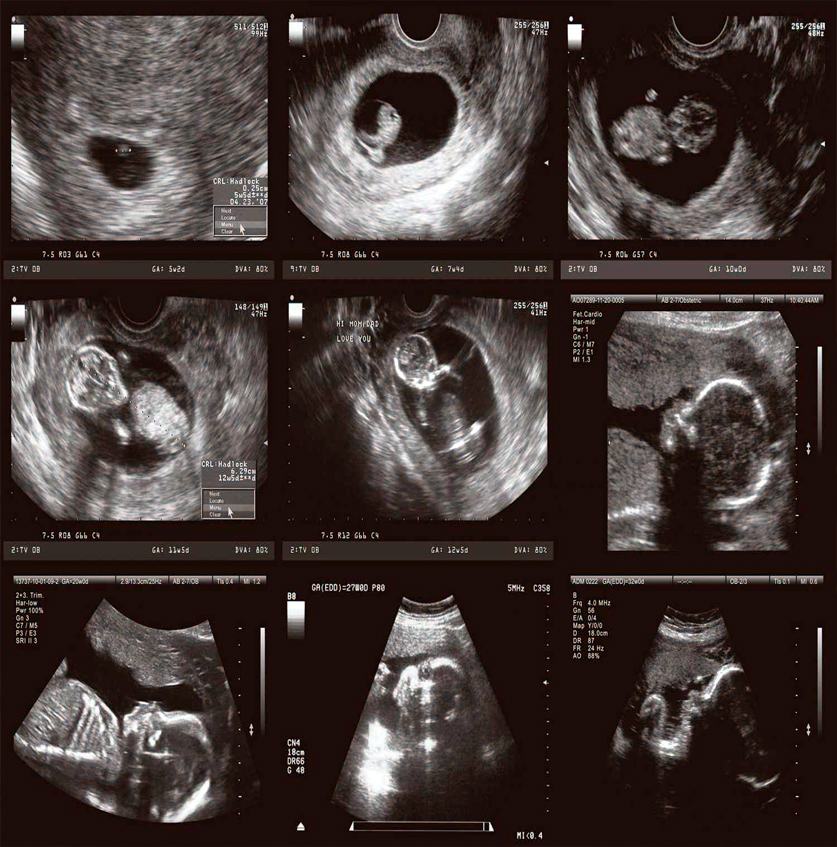

Gebe takibi, anne adayının ve bebeğin sağlığının gebelik öncesinden başlayarak doğuma kadar düzenli ve sistemli şekilde izlenmesini kapsayan çok önemli bir süreçtir. Op. Dr. Yurdanur Gürçay Açılmış, Gaziantep’te yürüttüğü gebe takibi hizmetlerinde, her anne adayını kendi sağlık durumu, yaşam tarzı ve gebelik özelliklerine göre bireysel olarak değerlendirir.

Gebeliğin ilk haftalarından itibaren yapılan kontrollerde annenin genel sağlık durumu, kan ve idrar testleri, ultrason incelemeleri ve gerekli tarama testleri düzenli olarak planlanır. Bebeğin gelişimi, kilosu, kalp atımları ve organ gelişimi yakından takip edilir. Olası risk faktörleri erken dönemde tespit edilerek gerekli önlemler zamanında alınır.

Op. Dr. Yurdanur Gürçay Açılmış, Gaziantep’te sunduğu gebe takibi sürecinde yalnızca tıbbi kontrollerle değil, anne adayının bilinçlendirilmesi, beslenme ve yaşam tarzı önerileri ile de gebeliğin sağlıklı ve güvenli bir şekilde ilerlemesini amaçlamaktadır. Hedef; hem anne hem de bebeğin doğuma en sağlıklı şekilde hazırlanmasını sağlamaktır.